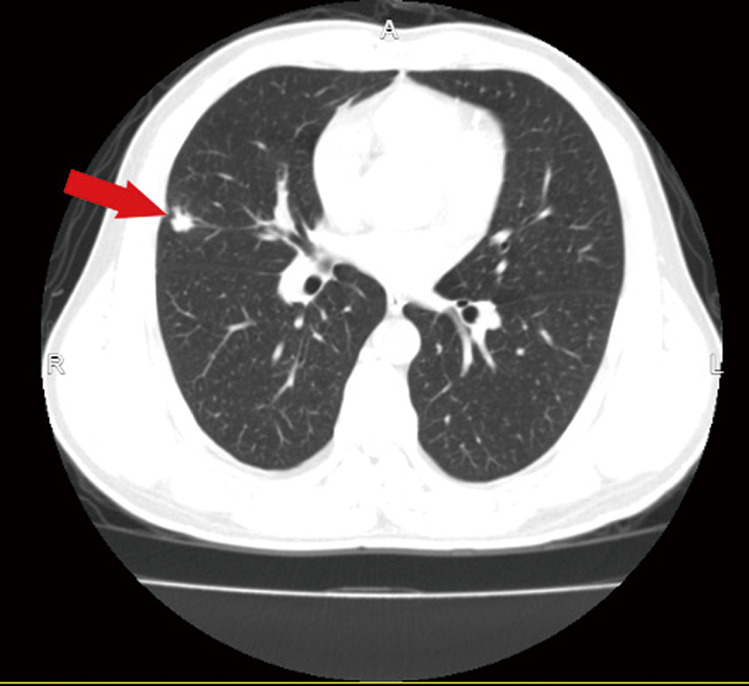

Case description: We report the case of a 49-year-old male who was diagnosed with stage IIIb (N2) lung adenocarcinoma. Next-generation sequencing revealed ROS1 fusions, and crizotinib was given simultaneously with targeted therapy during neoadjuvant chemotherapy. After 3 cycles of chemotherapy, surgery was performed, and the pathological results revealed major pathological response (MPR). Two years later, local and general examinations revealed no evidence of tumour recurrence.